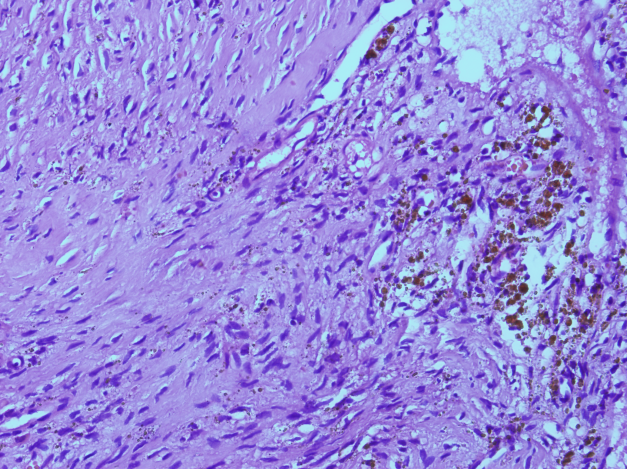

El paciente fue sometido a una descompresión neuroquirúrgica de la lesión lumbar. El estudio anatomo patológico (figura 6) mostró una reacción fibrohistiocítica con formación de hueso reactivo y cambios de quiste óseo aneurismático en relación con tumor pardo debido a hiperparatiroidismo.

En pacientes con hiperparatiroidismo, el exceso de PTH resulta en una actividad osteoclástica incrementada y resorción ósea con fibrosis reactiva subsecuente. Los tumores pardos se producen a partir de la fusión de los quistes que se desarrollan durante la progresión de la resorción focal de la médula ósea y fibrosis (7,12). En la tinción con hematoxilina eosina (H&E) estos tumores están compuestos de focos de hemosiderina y células gigantes tipo osteoclastos, dentro de un estroma fibrovascular consistente en fibroblastos densos en una matriz ricamente vascularizada (7). La coloración macroscópica parda de estos tumores se debe a los depósitos de hemosiderina que contienen. (11)